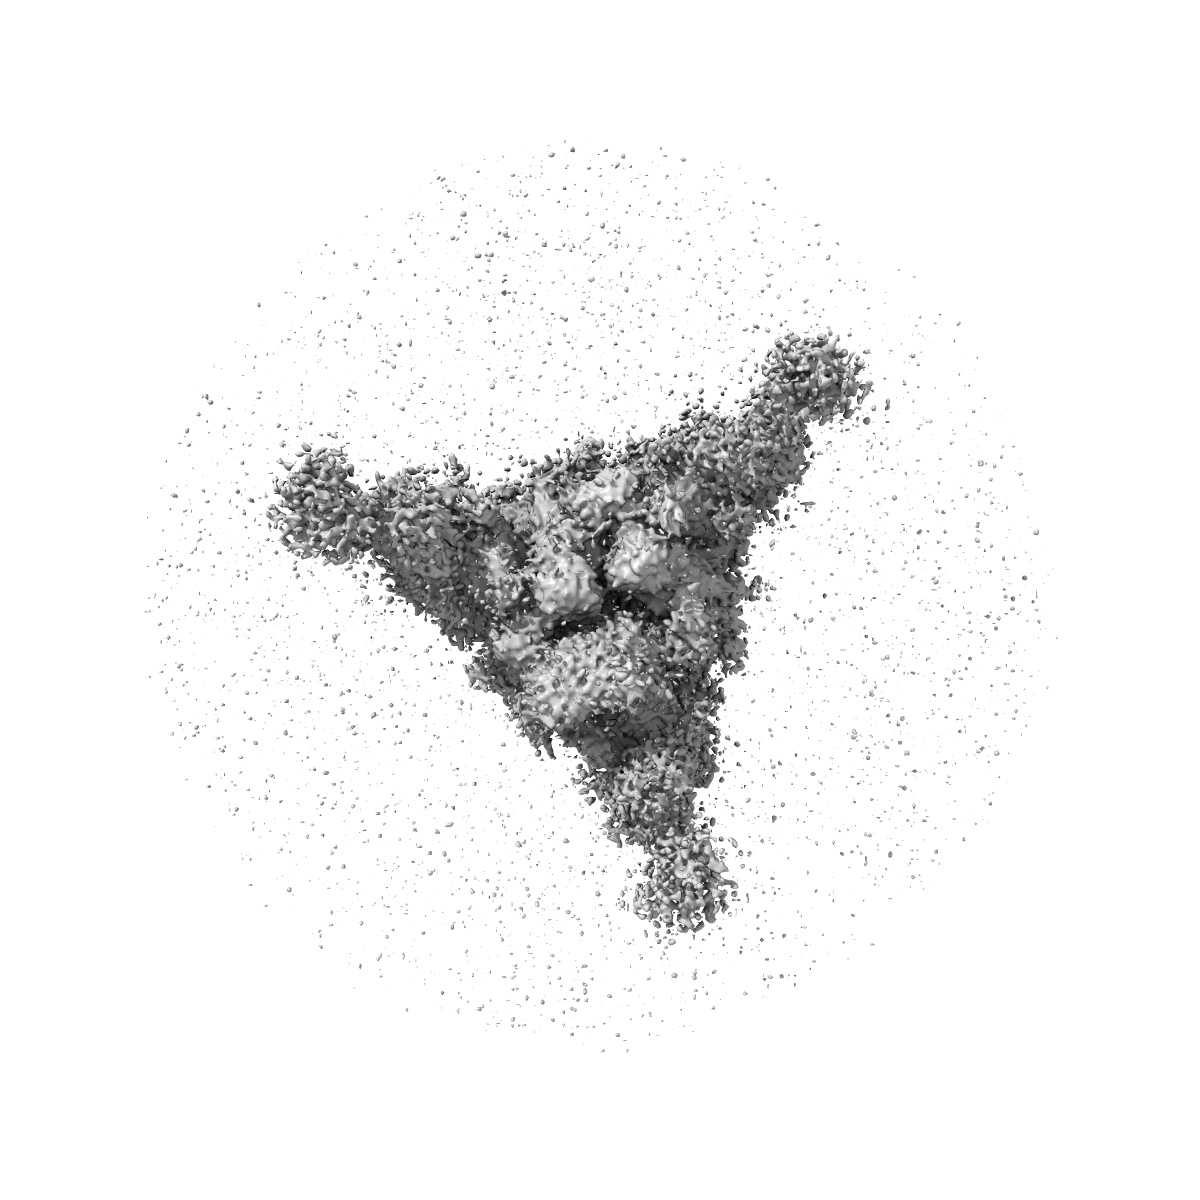

Cryo-EM structure of NTD-directed neutralizing antibody 4-8 Fab in complex with SARS-CoV-2 S2P spike

Single-particle3.25 Å

Sample: 4-8 Fab in complex with SARS-CoV-2 S2P spike

Fitted models: 7lqv

Potent SARS-CoV-2 Neutralizing Antibodies Directed Against Spike N-Terminal Domain Target a Single Supersite